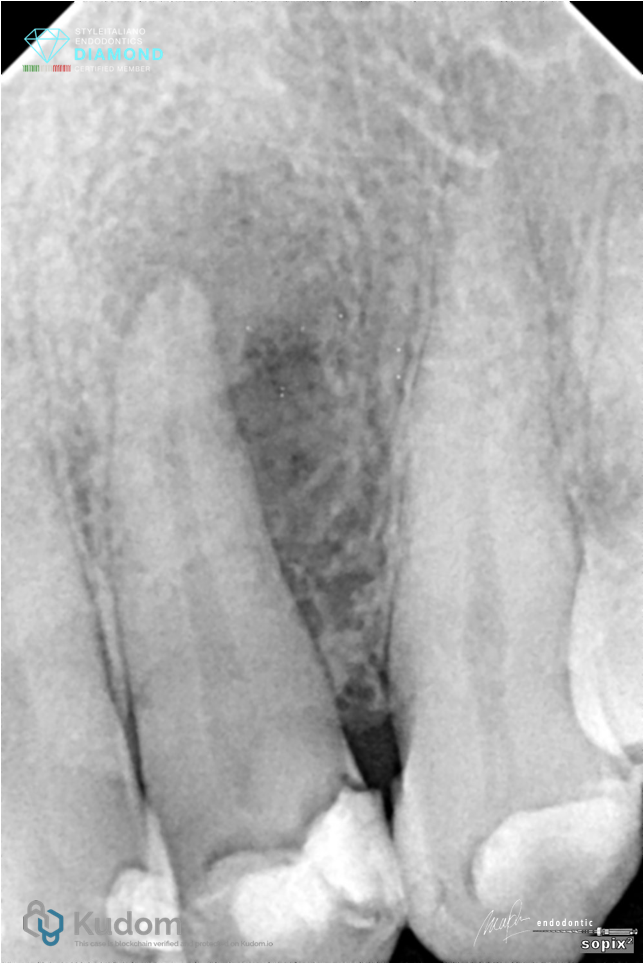

Fig. 5

Post op Xray showed an anatomical variations at the apical area. BC sealer managed to fill the spaces

Fig. 6

Another angle of post op Xray. Coronal restoration now showing good adaptation without void. And some anatomical variations at the apical area showed that C Root BC sealer managed to fill the spaces that has been adequately shaped and cleaned